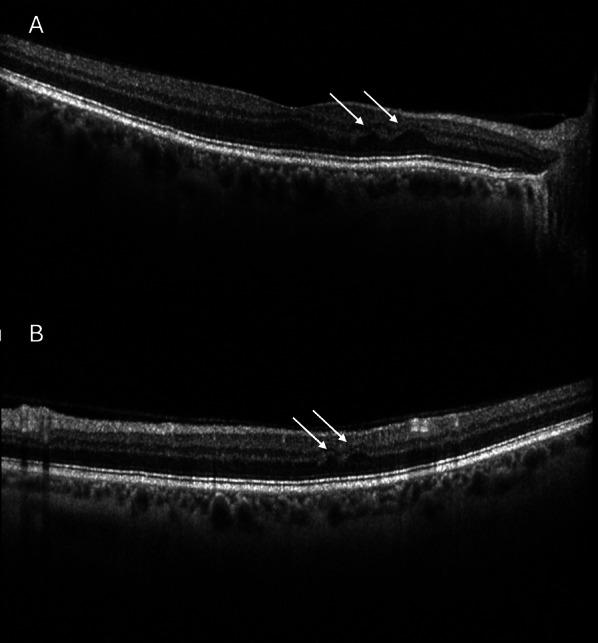

Retinal ischemic perivascular lesions (RIPLs) are characteristic focal thinning of the inner nuclear layer, with an upward expansion of the outer nuclear layer identified by spectral domain optical coherence tomography (SD-OCT), causing a focal irregular appearance of the middle retina. RIPLs result from retinal hypoperfusion in the deep capillary plexus, as a legacy of paracentral acute middle maculopathy, representing permanent anatomical markers of prior ischemic events. Although frequently found incidentally during routine eye examinations, RIPLs may provide insights into subclinical vascular damage that underpins various cardio- and cerebrovascular diseases. The aim of this narrative review is to summarize the relationships of RIPLs with retinal and systemic vascular diseases, including arterial hypertension, coronary artery disease, carotid artery stenosis, atrial fibrillation, stroke, sickle cell disease, and diabetes mellitus. Cardiovascular and metabolic diseases, which are the leading causes of morbidity and mortality worldwide, often remain asymptomatic for years despite early structural changes until severe adverse events occur. Noninvasive retinal biomarkers such as RIPLs, which are readily and noninvasively detected through SD-OCT scans, could help in the early detection and stratification of patients at risk for cardiovascular diseases, facilitate timely medical interventions and lifestyle changes, and ultimately improve disease prevention in a "personalized medicine" approach. While further research is needed to establish the prevalence of RIPLs in the general population and their full clinical significance, advances in ophthalmic imaging technologies combined with rapid progress in artificial intelligence applications in medical research could accelerate the development of RIPLs in retinal imaging-based oculomics.

视网膜缺血性血管周围病变(RIPLs)是内核层特征性的局灶性变薄,通过光谱域光学相干断层扫描(SD-OCT)可发现外核层向上扩展,导致视网膜中层出现局灶性不规则外观。RIPLs是由深层毛细血管丛视网膜灌注不足引起的,是中心旁急性黄斑病变的遗留表现,代表先前缺血事件的永久性解剖学标志。尽管RIPLs在常规眼部检查中经常偶然发现,但它们可能为各种心血管和脑血管疾病潜在的亚临床血管损伤提供见解。本叙述性综述的目的是总结RIPLs与视网膜和全身血管疾病的关系,包括动脉高血压、冠状动脉疾病、颈动脉狭窄、心房颤动、中风、镰状细胞病和糖尿病。心血管和代谢疾病是全球发病和死亡的主要原因,尽管早期结构发生改变,但在严重不良事件发生之前,这些疾病往往多年无症状。像RIPLs这样的非侵入性视网膜生物标志物可通过SD-OCT扫描轻松、无创地检测到,有助于早期发现和分层心血管疾病风险患者,促进及时的医疗干预和生活方式改变,并最终以“个性化医疗”方法改善疾病预防。虽然需要进一步研究以确定RIPLs在普通人群中的患病率及其全部临床意义,但眼科成像技术的进步与医学研究中人工智能应用的快速发展相结合,可能会加速基于视网膜成像的眼组学中RIPLs的发展。